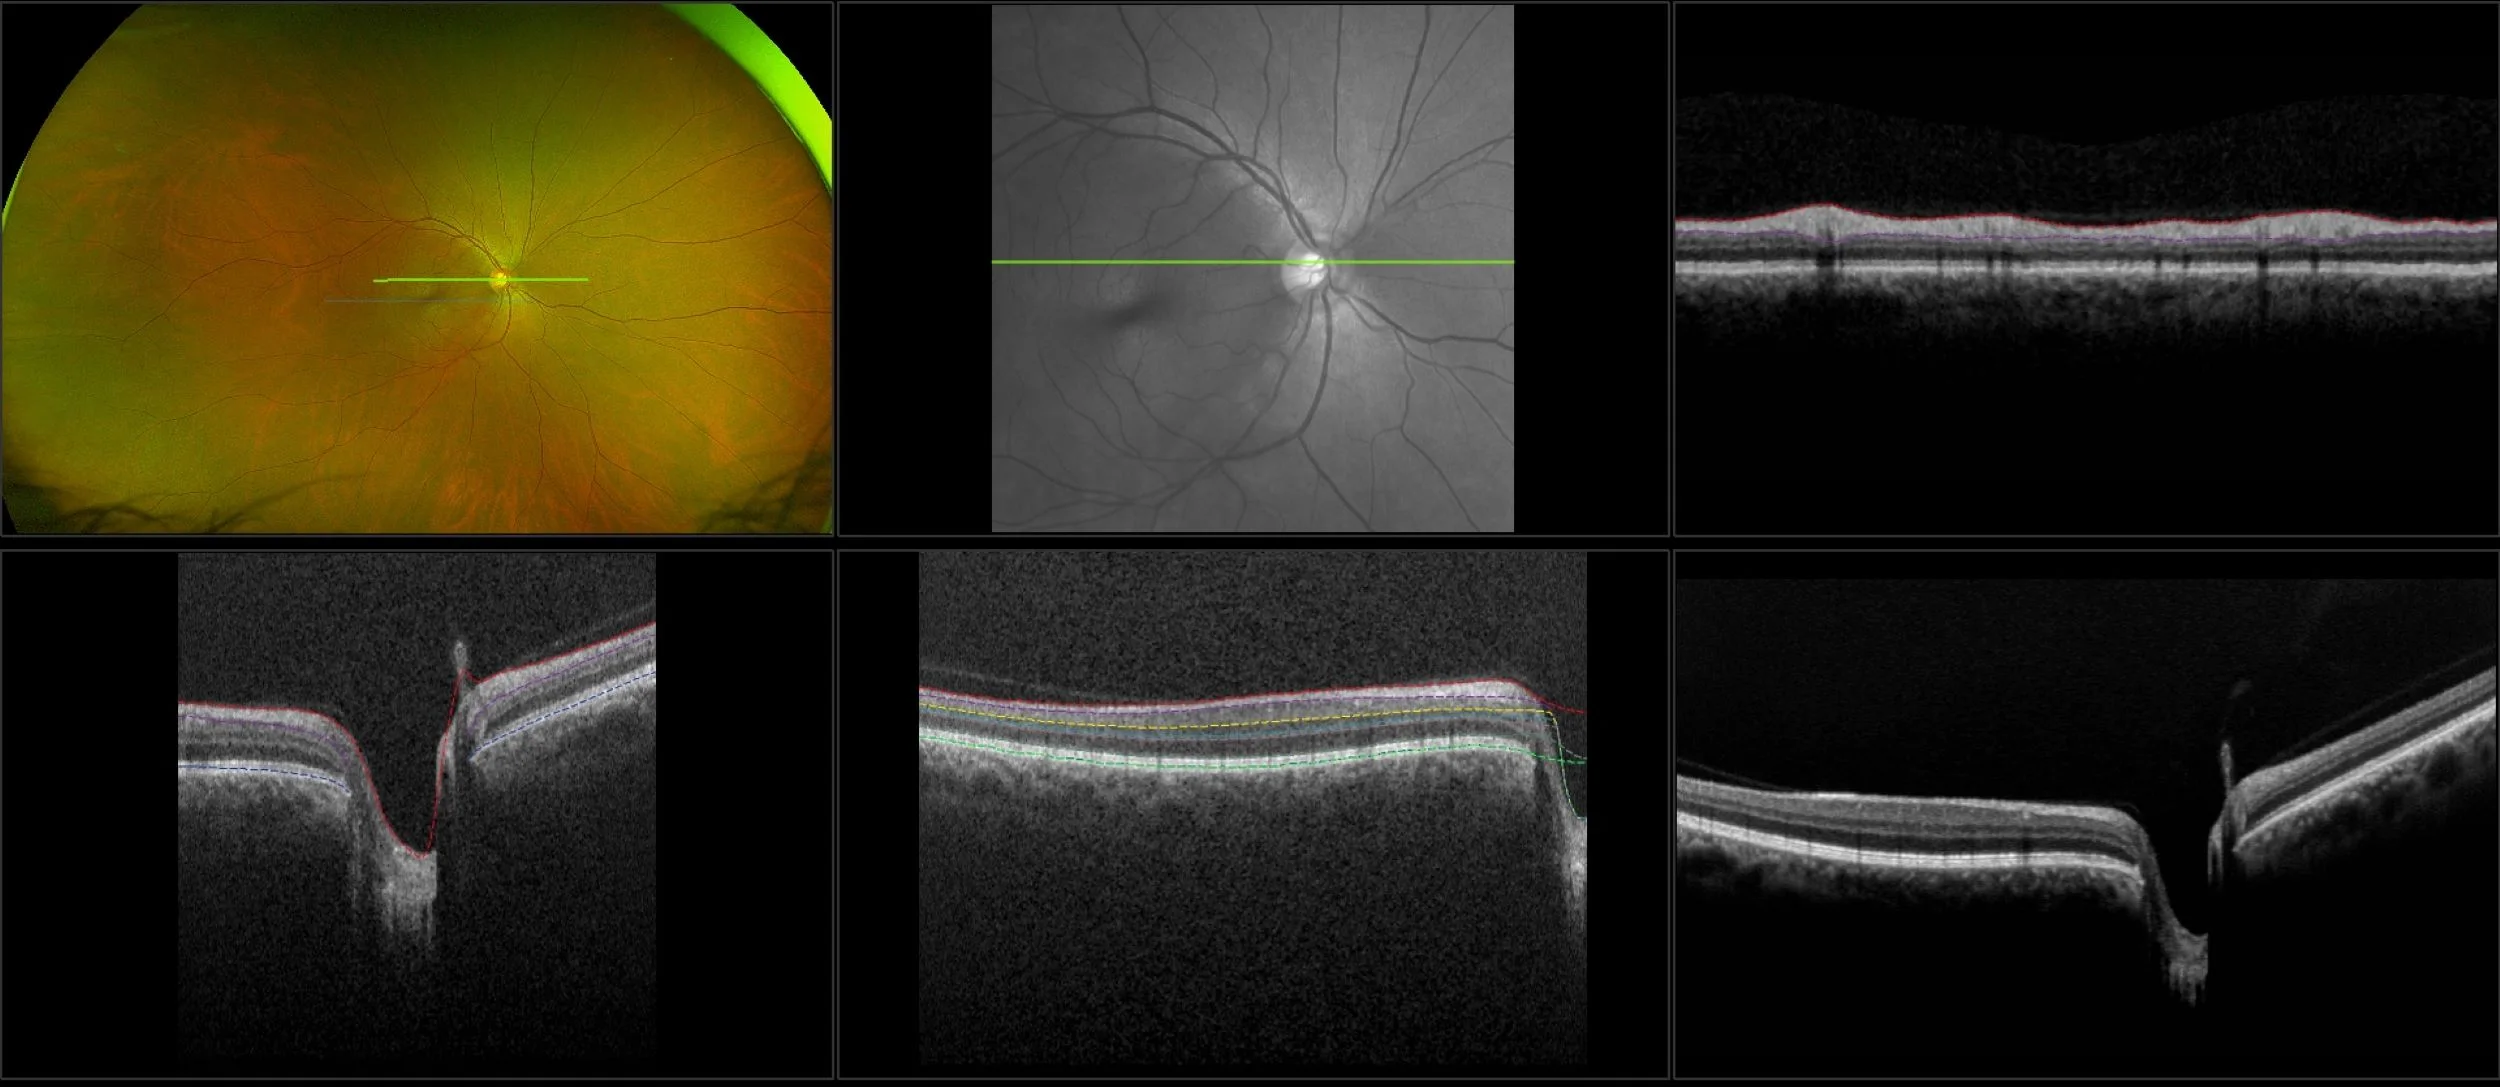

This material is designed as a searchable reference resource to support clinical decision-making. The information contained here should be used as general guidance when viewing optomap and OCT images from Optos devices. The differential diagnosis should be made under the direction of the responsible physician. These images were taken on the latest ultra-widefield optomap devices.

optomap Recognizing Pathology is searchable by pathology and/or optomap image modality. You may search by multiples of each selection. Each individual case is represented by the accompanying thumbnail image. Most cases include several different optomap image modalities. To view a full description of the case, please click on the thumbnail. Each image in the case will be made available through our OptosAdvance software which provides multi-dimensional visualization of digital images to aid in the analysis of anatomy and pathology. Support and pathology definitions can be found by selecting one of the buttons, above. Should you have questions, please complete the form below.